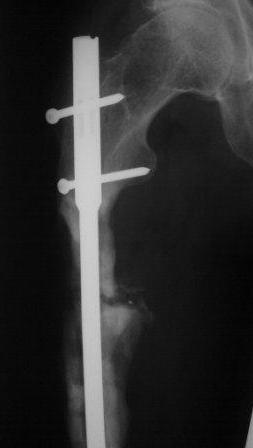

Продолжение случая от 12 января 2009 года.

Представляю контрольные послеоперационные рентгенограммы. Во время операции была

выделена зона перелома небольшим разрезом, произведена декортикация. Окончательный

остеосинтез. Все участникам обуждения большое спасибо за советы и рекомендации.